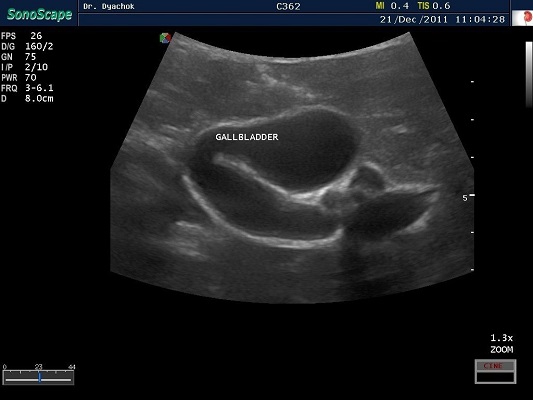

SonoScape S2N Vet – уникальная узи-система, выполненная в виде портативного ноутбука для легкой переноски. Отличается эта система цветным форматом визуализации, а также крайне чувствительными доплеровскими режимами, работающими на уровне премиальных аппаратов. При оптимальной цене – это очень хорошее и сбалансированное решение для ветеринарной клиники.

Диагональ монитора составляет 15,6 дюймов, что обеспечит комфортную работу для врачей и полный спектр визуализации для пациентов. Компактный вес не превышает 5 кг. (вместе с батареей), что оценят выездные бригады скорой помощи или ветеринары, выезжающие на дом.

• В, М, В/М, В/В, 4В, Тканевая гармоника, Пульсовая инверсная гармоника, Навигация биопсийной иглы (биопсийные направляющие), Режим улучшенной визуализации (подсветки) биопсийной иглы

• Изменение масштаба изображения в режимах реального времени и стоп-кадра

• Цветной, энергетический, направленный энергетический, направленный энергетический с высокимм пространственным разрешением, импульсно-волновой, постоянно-волновой доплер, тканевой доплер (опция)

• Дуплексный, триплексный режимы

• Трапецеидальное сканирование на линейных и конвексном датчиках

• Анатомический М-режим (опция), Цветной М-режим (опция), Панорамное сканирование (опция)

• Технология подавления спекл-шума MicroScan